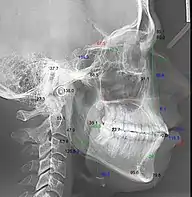

Телерентгенография с кефалометрическим анализом

Кефалограмма — это геометрическая обрисовка телерентгенограммы для изучения абстрактных закономерностей — угловых и линейных кефалометрических параметров.[3][4]